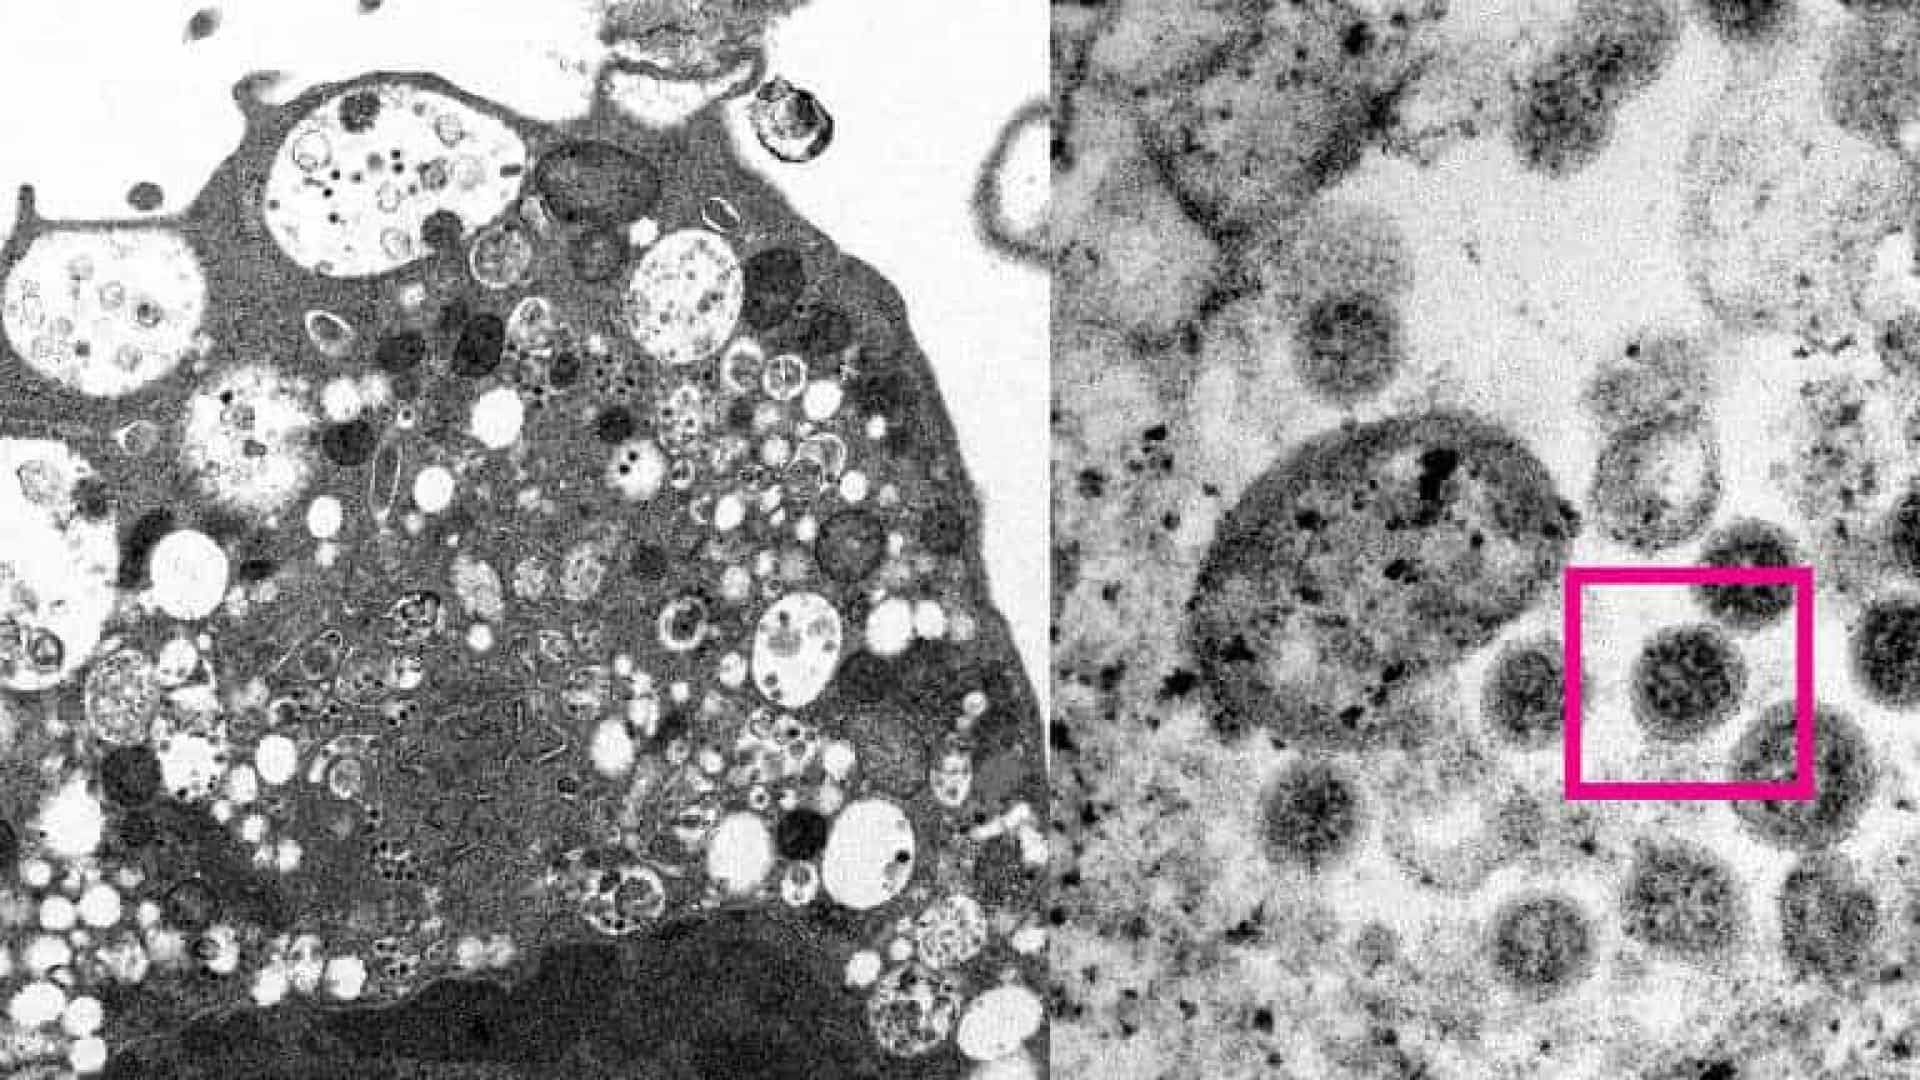

À esquerda da imagem, é possível ver uma célula de um rim de macaco após infecção com a variante ômicron. A foto mostra alguns danos celulares com vesículas inchadas e contém pequenas partículas virais em cor preta.

Já a parte direita da imagem, vê-se uma célula infectada. Na parte que tem uma caixa vermelha, observa-se partículas virais com pontas em forma de coroa.